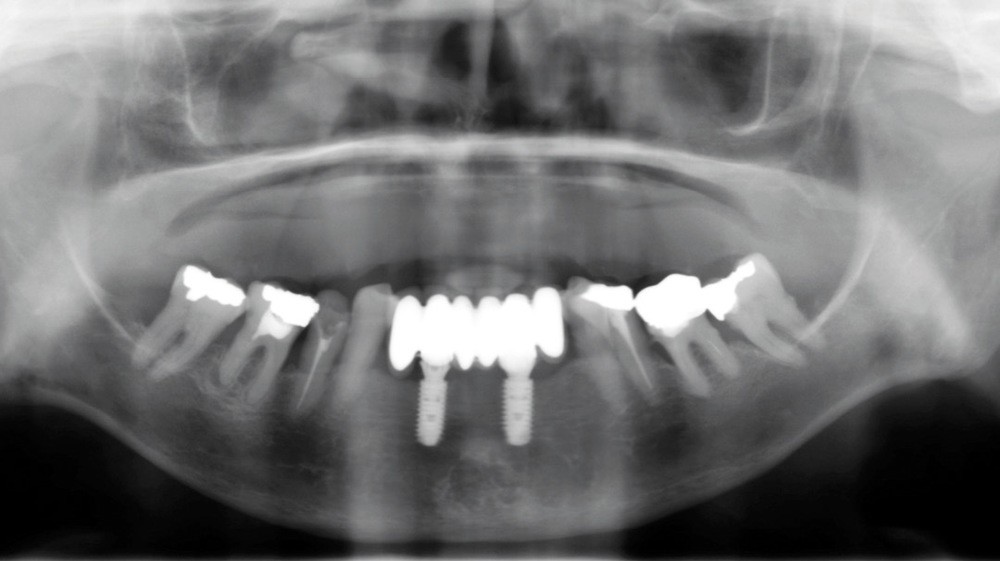

1. Le déprogrammeur occlusal est fabriqué sur le modèle en plâtre maxillaire.